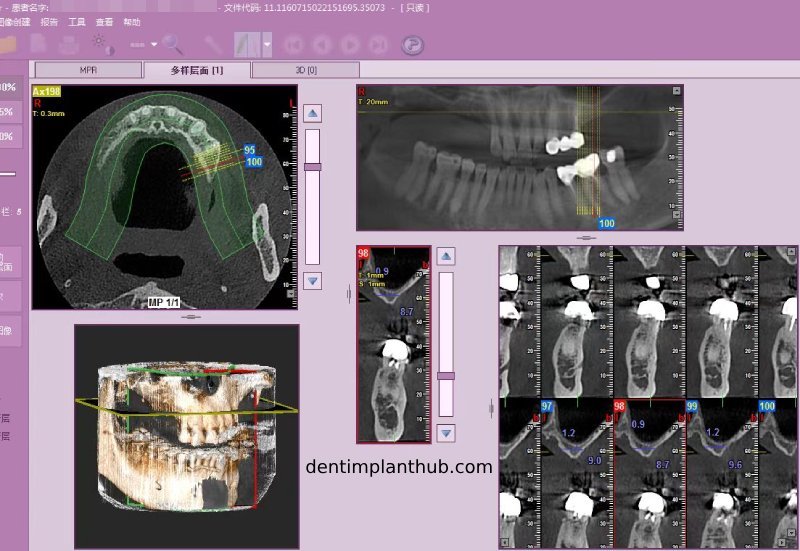

Screenshot of repeat CT on 7/1/25